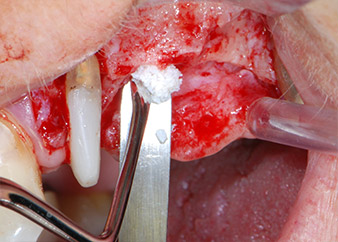

Bone deficiencies around the implants, at the mesial aspect of tooth 27 and around the buccal root of tooth 24, were filled with xenogeneic bone substitute particles and covered with an absorbable collagen membrane (Bio-Gide, Geistlich Biomaterials) for GBR augmentation (Figs. 13 and 14).

Xenogeneic bone substitute material

Fig. 13: Xenogeneic bone substitute material was used to fill the remaining osseous defects …

absorbable collagen membrane

Fig. 14: ... which was then covered with an absorbable collagen membrane. The grayish-pink structure between the elevators at the top margin of the picture represents interproximal papillary tissue.